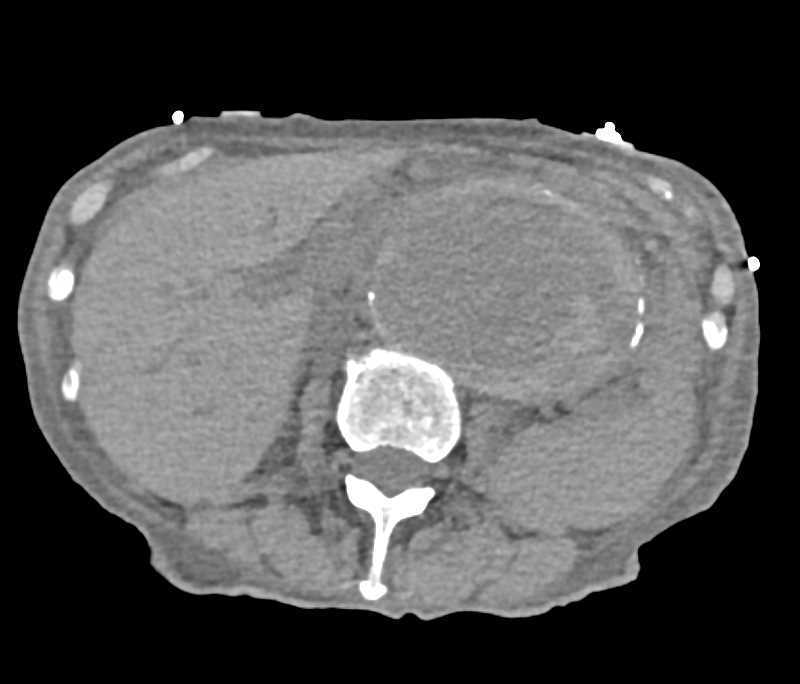

CTA Runoff with Superficial Femoral Artery (SFA) Spasm due to GSW